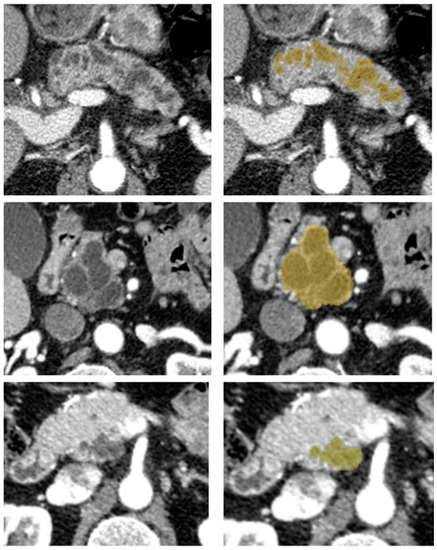

2.6. Segmentation